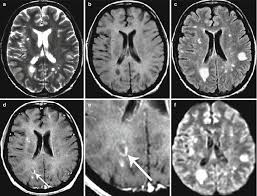

Recent papers in demyelinating disease. A demyelinating disease is any disease of the nervous system in which the myelin sheath of neurons is damaged. Meaning of demyelinating disease medical term. This topic contains 250 study abstracts on demyelinating diseases indicating that the following substances may be helpful: Multiple sclerosis is a progressive disease that is five.

This topic contains 250 study abstracts on demyelinating diseases indicating that the following substances may be helpful: These disorders may be inflammatory, infective. Meaning of demyelinating disease in english. Demyelinating disorders are a subgroup of white matter disorders characterised by the destruction or damage of normally myelinated structures. Demyelinating disorders of the brain and spinal cord. Multiple sclerosis is a progressive disease that is five. Brain signals can't move across scar tissue as quickly, so your nerves don't work as. Overview of signs & symptoms consistent with demyelinating disease with links to information and resources for patients. Ms is the most common demyelinating disease. It is characterized by demyelination in the brain, spine, and/or optic nerve. A disease that damages myelin (= a white fatty substance that covers some nerves): Meaning of demyelinating disease medical term. Vitamin d, cannabis, and cannabinoids.

A disease that damages myelin (= a white fatty substance that covers some nerves): Several conditions lead to demyelination and one of the most well known of the neurodegenerative disorders is multiple sclerosis. What are demyelination diseases characterized by? This topic contains 250 study abstracts on demyelinating diseases indicating that the following substances may be helpful: Demyelinating diseases can be classified into those which affect the central nervous system and those which affect the peripheral nervous system.

View demyelinating disease research papers on academia.edu for free. A demyelinating disease is any disease of the nervous system in which the myelin sheath of neurons is damaged. Demyelinating disease autoimmune disease chronic inflammatory demyelinating polyneuropathy guillain barre demyelinating disease autoimmune disease cidp numb sorting diabetes health. In turn, the reduction in conduction ability causes deficiency in sensation, movement, cognition. Demyelination describes the loss of the myelin sheath, where sc are being destroyed or unwrapped from axons (15). Meaning of demyelinating disease in english. This damage impairs the conduction of signals in the affected nerves. Demyelination can lead to pain, numbness, and other symptoms. Demyelinating disorders are any conditions that damage myelin. Brain signals can't move across scar tissue as quickly, so your nerves don't work as. Demyelinating disorders are a subgroup of white matter disorders characterised by the destruction or damage of normally myelinated structures. Classification of the demyelinating diseases is done on the basis of whether they are affecting the nerves of the central nervous system or of the peripheral nervous system. When this happens, scar tissue forms in its place.